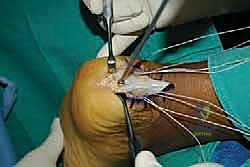

- الشق الجراحي: يتم عمل شق طولي دقيق (غالباً في المنتصف أو من الجانب) للوصول إلى منطقة ارتكاز الوتر وعظم الكعب.

- استئصال الجراب الملتهب: يتم إزالة الأكياس الزلالية الملتهبة (Bursa) التي تسبب جزءاً كبيراً من الألم.

- فصل الوتر (الجزئي أو الكلي): للوصول إلى النتوء العظمي والتكلسات، يضطر الجراح لفصل جزء من وتر أخيل من مكان ارتكازه.

- استئصال تشوه هاغلوند والتكلسات: باستخدام أدوات جراحية دقيقة، يتم قص وإزالة النتوء العظمي البارز بالكامل، وتسوية سطح عظم الكعب لضمان عدم احتكاكه بالوتر مستقبلاً. كما يتم إزالة أي تكلسات عظمية نامية داخل ألياف الوتر نفسها.

- التنضير (Debridement): يقوم الجراح بقص وإزالة كافة الأنسجة الميتة، المتهالكة، والتنكسية من الوتر، مع الحفاظ على الألياف السليمة والقوية.

- إعادة التثبيت باستخدام الخطاطيف (Suture Anchors): هذه هي المرحلة الأهم والتي تعتمد على التكنولوجيا الحديثة. يتم زرع خطاطيف دقيقة (مصنوعة من التيتانيوم أو مواد قابلة للامتصاص) داخل عظم الك